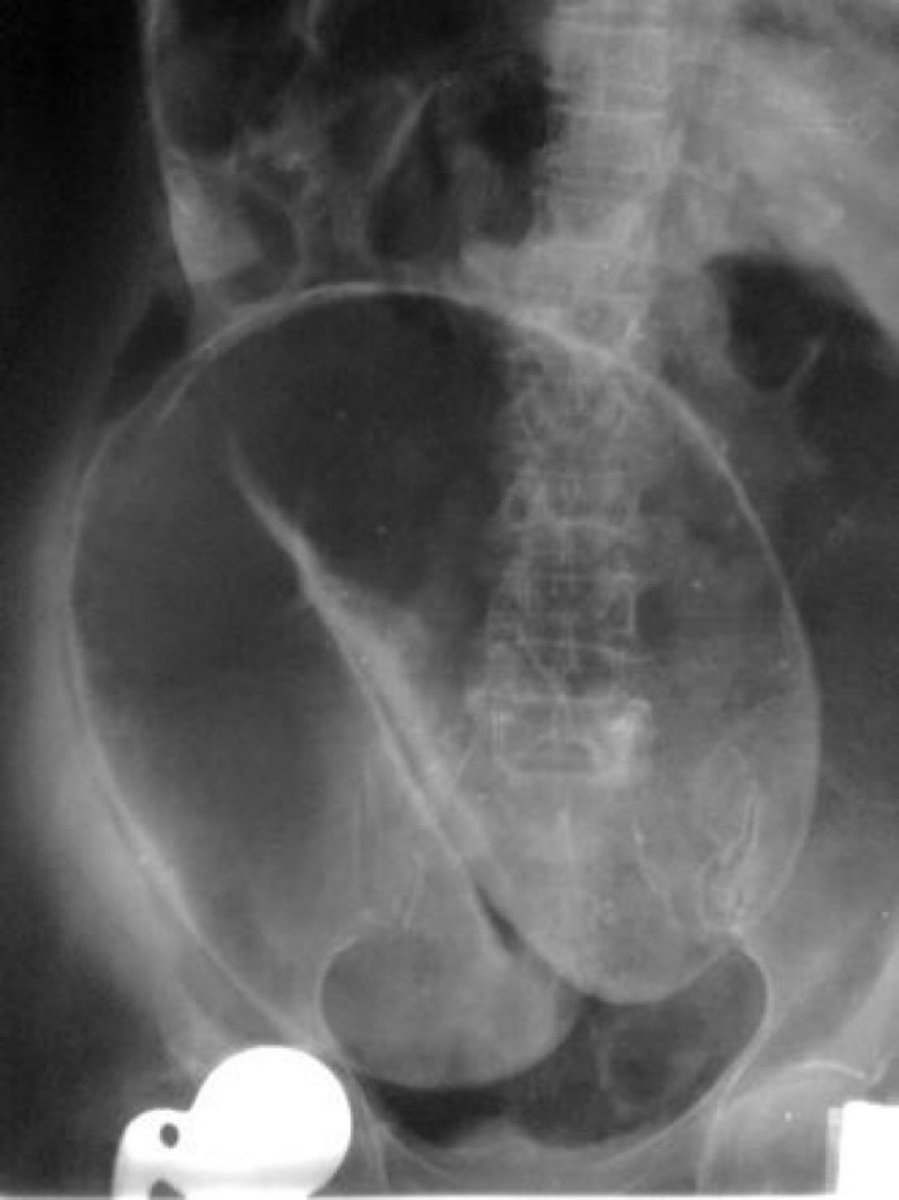

Заворот желудка причины 85 фото